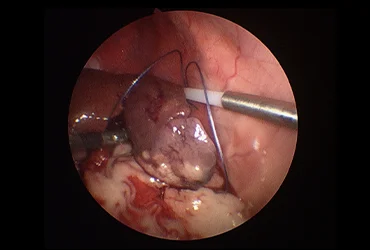

(진단/협진 사례: 간염 환자의 복강경 생검, 간종양 환자의 경우 외과 협진을 통한 복강경 종양 제거 계획 수립)

치료 과정에서 외과와의 긴밀한 협력을 통해 담낭 절제, 종양 제거, 장관 이물 제거 등 필요한 수술적 처치를 원활하게 연계하며,